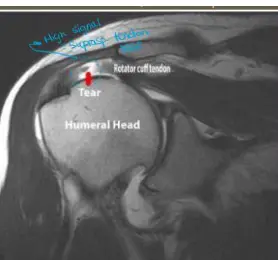

Question 56 - A 45-year-old male with anterior shoulder dislocation. Which injury is demonstrated in the attached MRI?

- d. Supraspinatus tear

Question: A case scenario that was suggestive of an anterior shoulder dislocation in a 45-year-old male. Which of the following injuries is demonstrated in the attached MRI?

- Answer: Supraspinatus tear